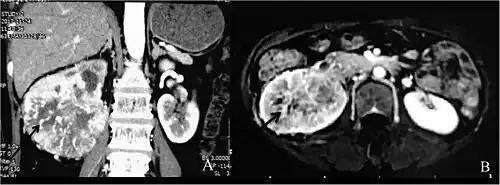

Individuals with Dioctophyme renale infection (known as dioctophymosis) typically present with unspecific symptoms including hematuria[1][3] (blood in urine), nephritis, loin pain,[7] renal enlargement, and/or renal colic[1] (intermittent pain in the kidney area), which may result from the rare migration of worms through ureters.[5][7][1][3] In some cases the fibrosis occurring after parasite infection is an incidental finding in ultrasound or CT scan, mimicking renal cancer, leading to radical nephrectomy.[11]

- ↑ Katafigiotis, Ioannis; Fragkiadis, Evangelos; Pournaras, Christos; Nonni, Afrodite & Stravodimos, Konstantinos G. (October 2013). "Case Report: A rare case of a 39-year-old male with a parasite called Dioctophyma renale mimicking renal cancer at the computed tomography of the right kidney". Parasitology International. 62 (5): 459–60. doi:10.1016/j.parint.2013.06.007. PMID 23811203.